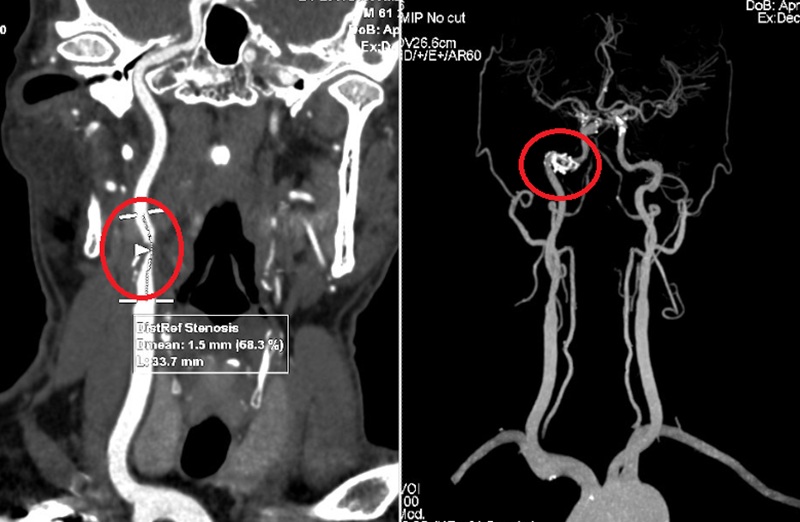

Theo ThS.BS Phạm Duy Hưng - Phó trưởng khoa Nội, Bệnh viện Đa khoa MEDLATEC, kết quả cấy máu bằng máy cấy tự động cho thấy bệnh nhân dương tính với vi khuẩn Escherichia coli; chụp cắt lớp vi tính ổ bụng thấy hình ảnh nhu mô 1/3 giữa thận hai bên vị ngấm thuốc kém, xung quanh có thâm nhiễm mỡ, ưu thế quanh thận trái hướng đến hình ảnh viêm thận; các kết quả khác chưa thấy dấu hiệu bất thường.

Kết quả chụp CT ổ bụng của bệnh nhân hướng đến hình ảnh viêm thận